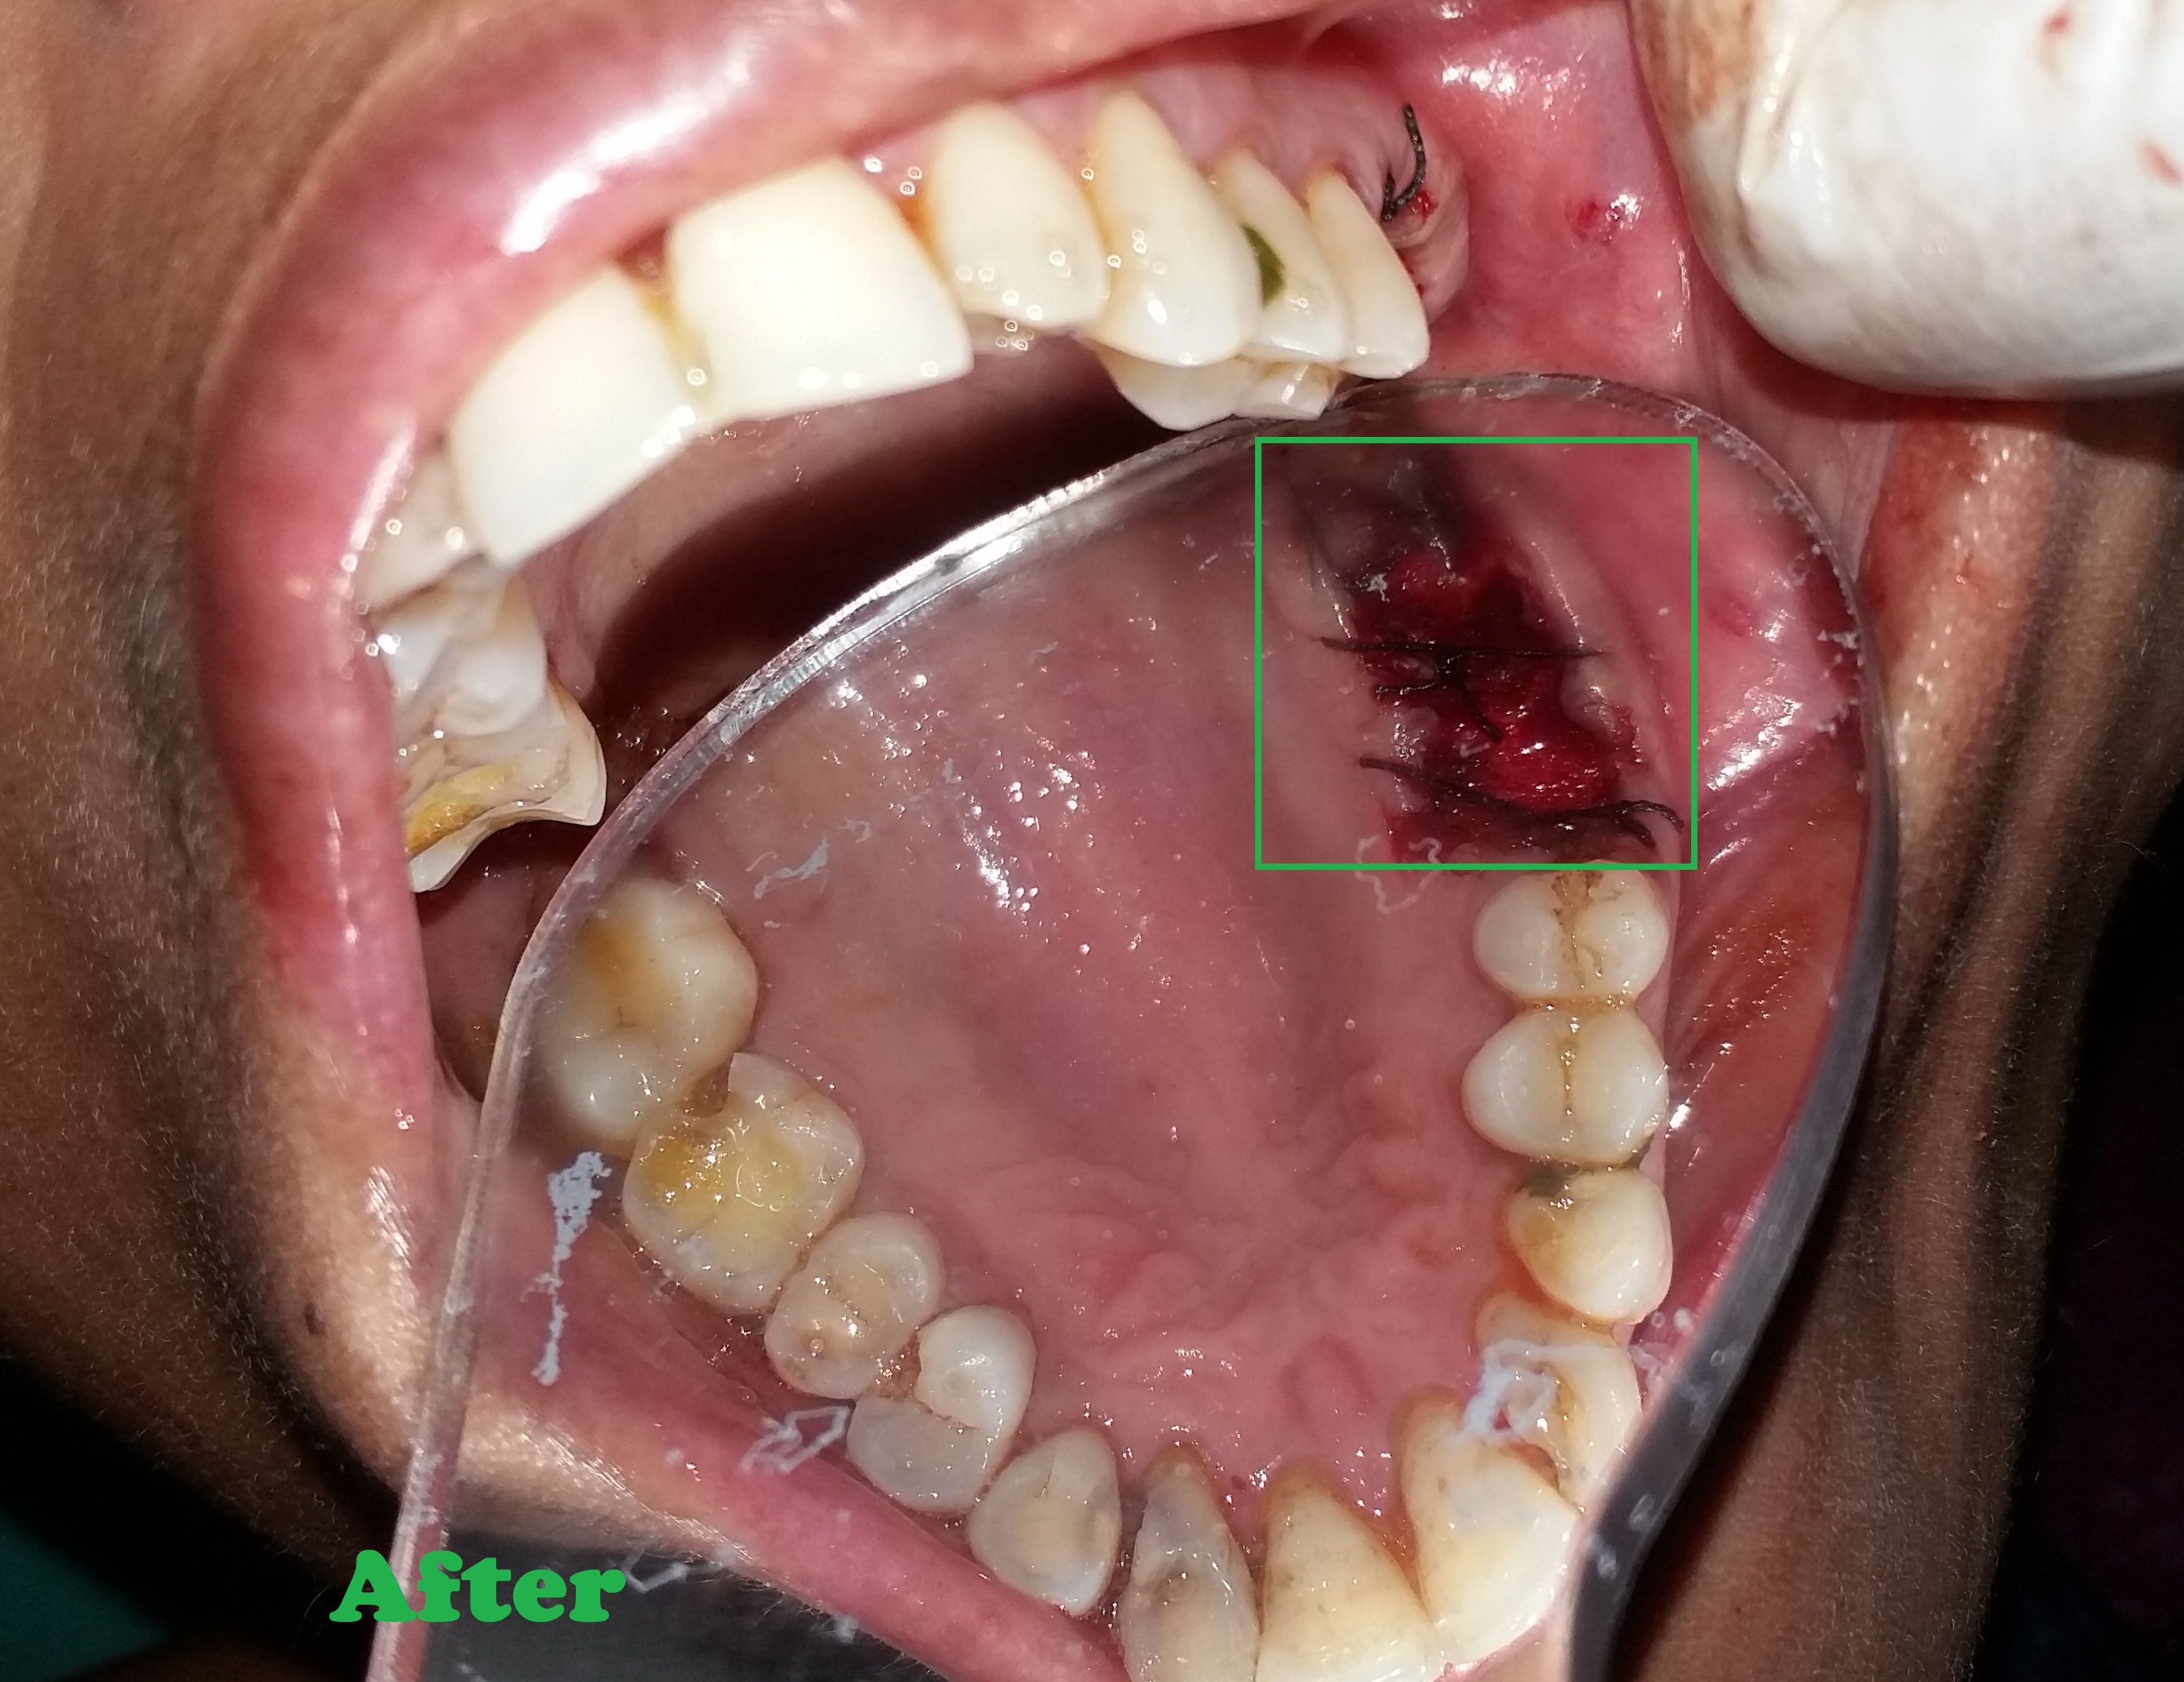

Root Canal Treatment

- Removes infected nerve tissue while preserving your natural tooth.

- Relieves pain, swelling, and sensitivity caused by deep decay or infection.

- Protects against tooth extraction and maintains natural biting ability.